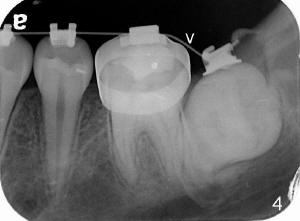

Impacted Lower 2nd Molar

Xin Wei, DDS, PhD, MS 1st edition 09/07/2011, last revision 09/07/2011